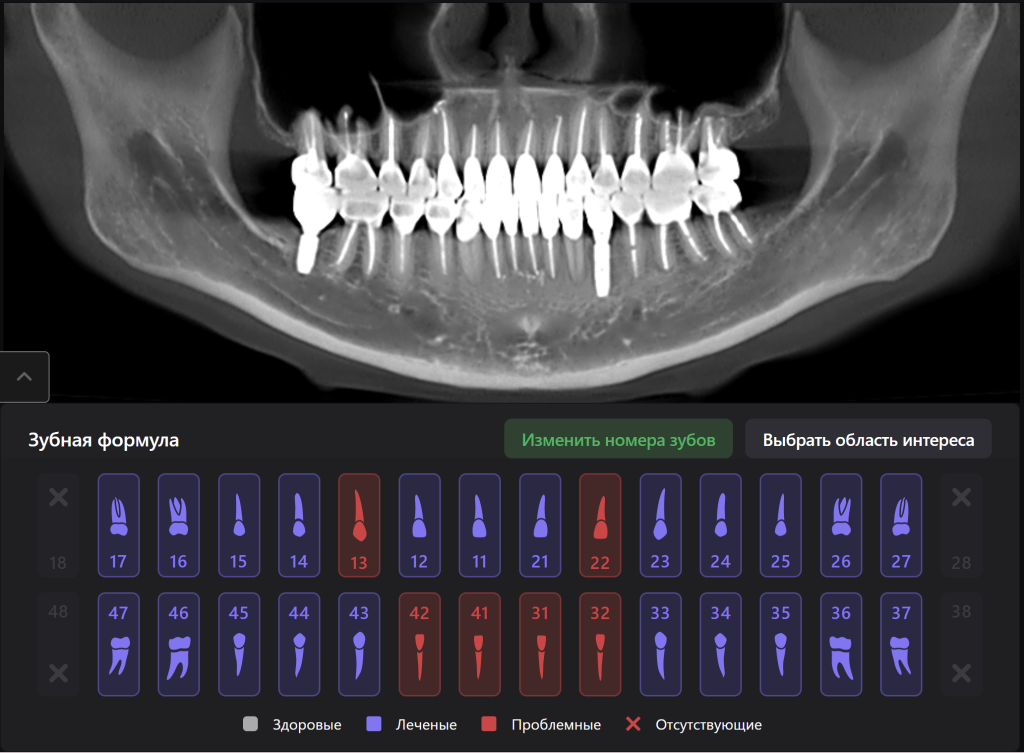

Пациентка обратилась с жалобами на неудовлетворительную эстетику зубных рядов. Выполнен полный диагностический комплекс, включающий КЛКТ исследование

Благодаря отчету Diagnocat планируем последовательность этапов терапевтической санации и имплантологического лечения. Обратите внимание, искусственный интеллект Diagnocat умеет различать такие патологии как «повышенная стираемость» и «клиновидный дефект» и отражает это в отчете

Через 18 месяцев от начала лечения выполнена повторная КЛКТ с анализом данных системой Diagnocat